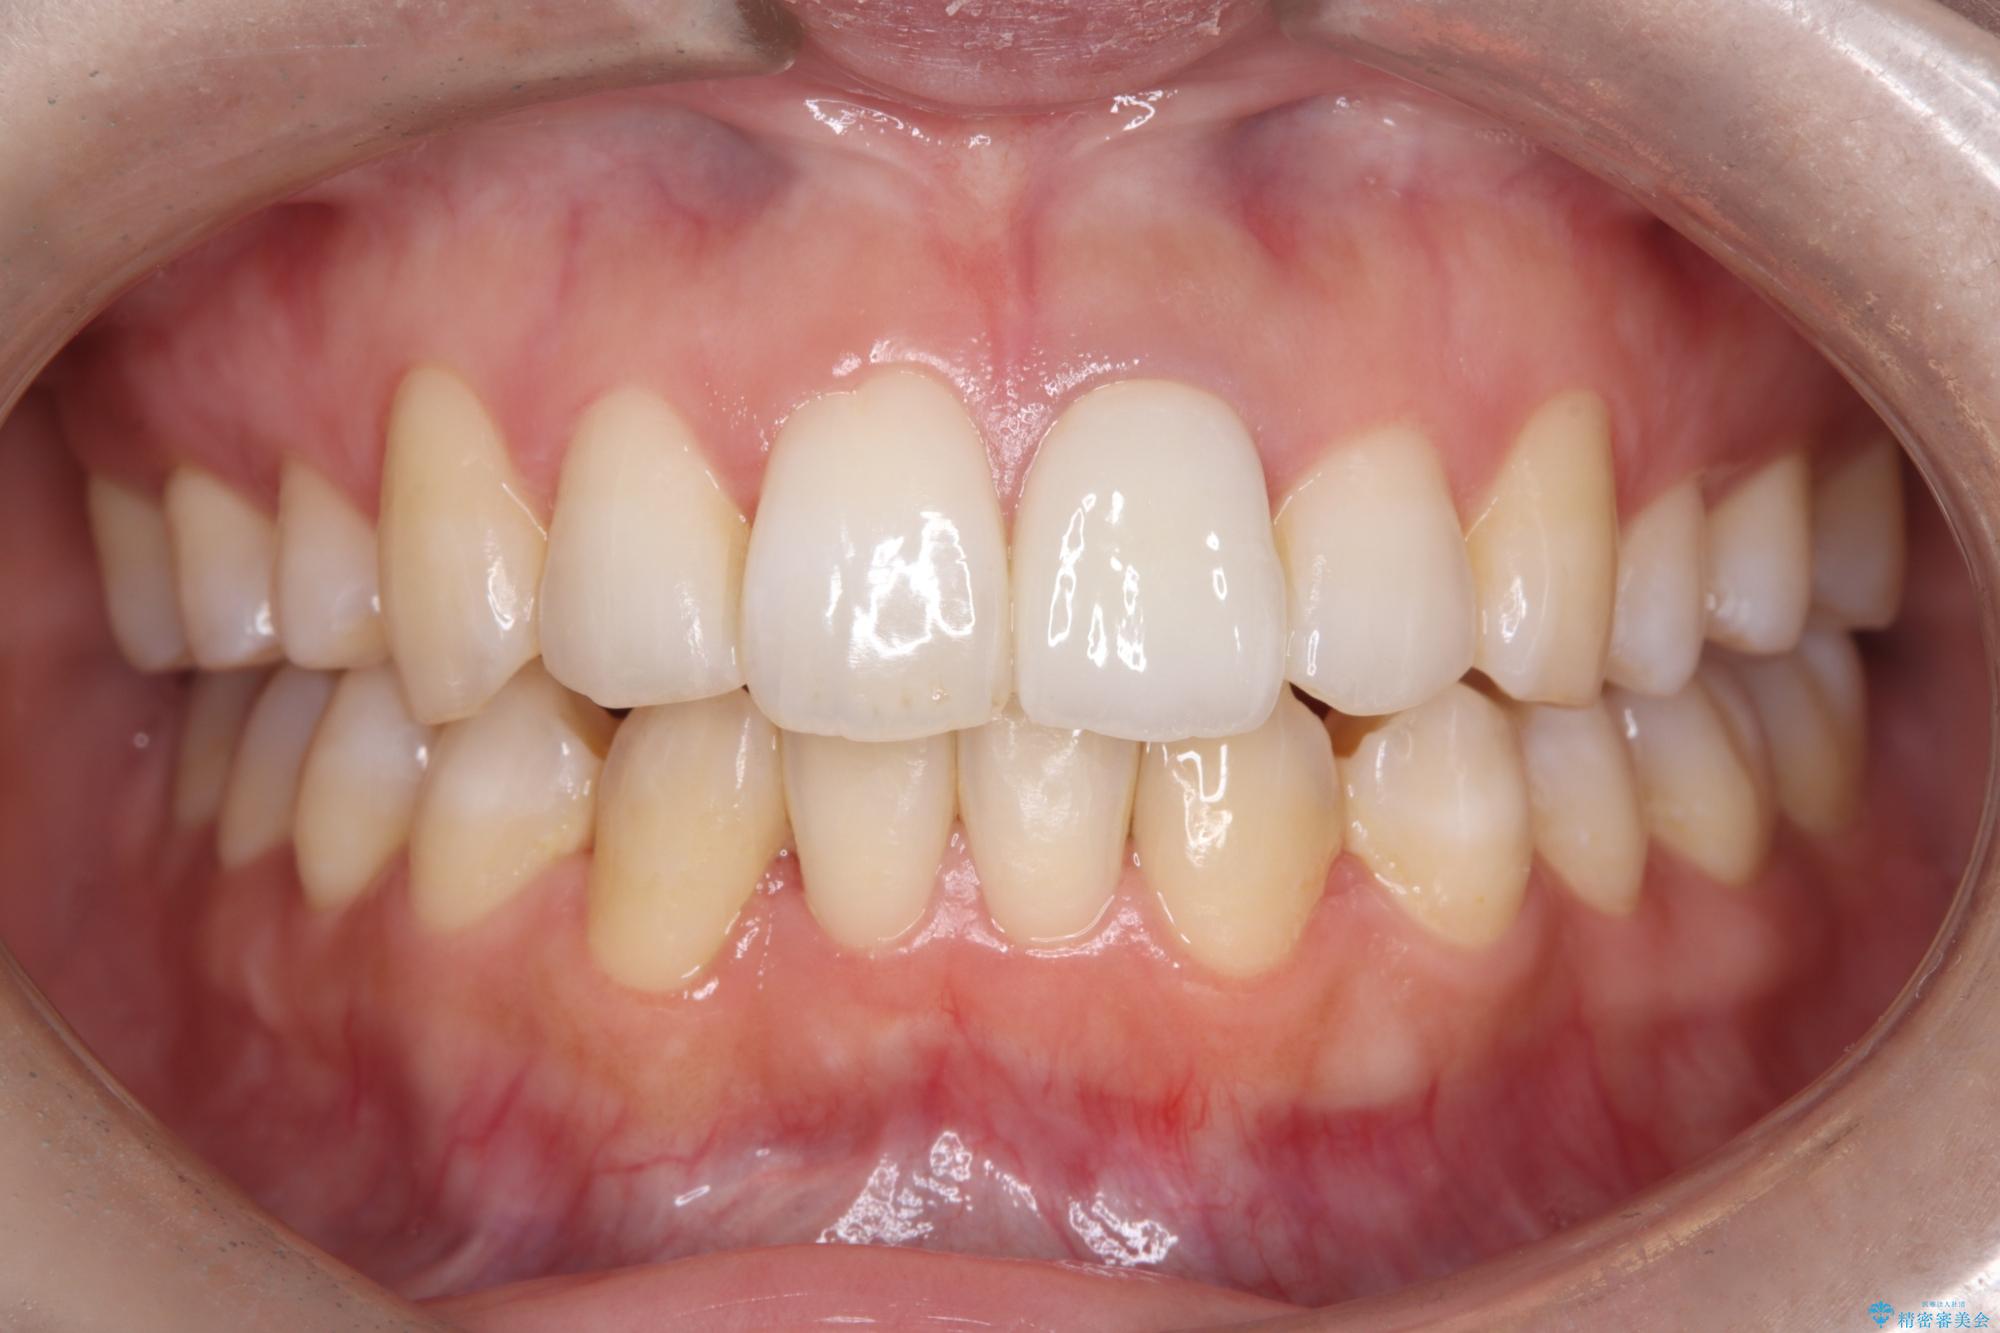

- 「以前、他院で神経を取った前歯がだんだん黒ずんできた」という見た目の改善を主訴にご来院されました。 診査の結果、神経を取り除いた後の歯(失活歯)特有の変色が起きており、さらに根の先端にわずかな影が見られたため、内部で感染が起きている可能性がありました。

そこで、まずは土台を外して根の内部をきれいにする再根管治療を行い、基礎をやり直した上で、透明感の高いオールセラミッククラウンで被せ直す治療計画を立案。単に白くするだけでなく、再発を防ぎ、長期的に美しい状態を保つことを目指しました。

オールセラミッククラウンによる修復: 最終的な被せ物には、一切の金属を使用しないオールセラミックを選択。隣の天然歯と色調や透明感を精密に合わせることで、どこを治療したかわからないほど自然な仕上がりとなりました。